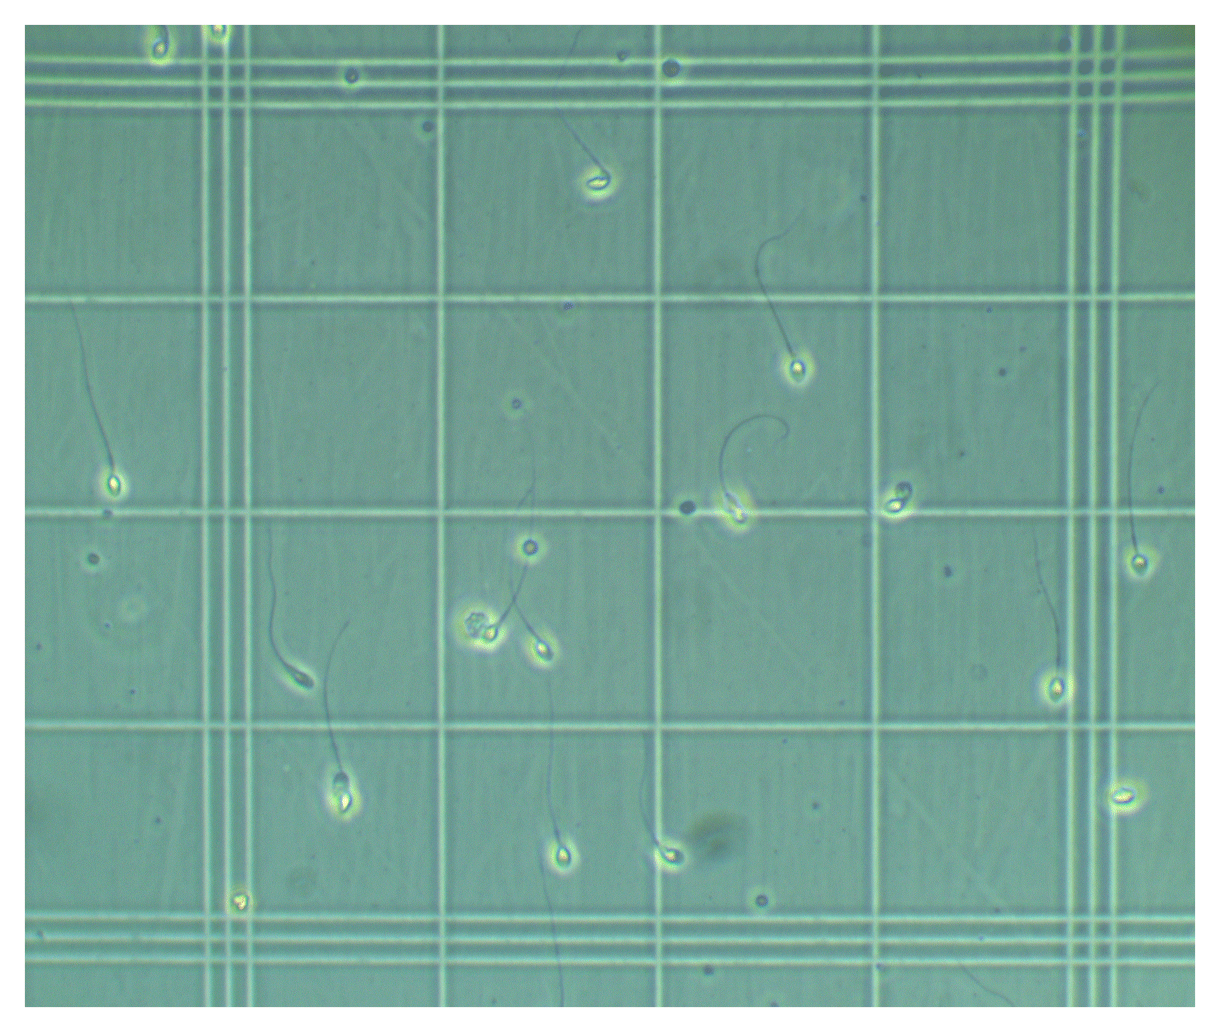

Anhand intelligenter Algorithmen ermöglicht unsere Software zur Spermiogrammanalyse die exakte automatische Bestimmung mikroskopischer Kennzahlen des männlichen Ejakulats: Konzentration, Motilität und bald auch Morphologie

Die tensorscope AI Algorithmen ermöglichen eine präzise Auszählung und Bestimmung von Spermien.

Der Seminal Analyzer übertrifft manuelle Auswertungsmethoden von Mikroskopanalysen an Effizienz und Genauigkeit